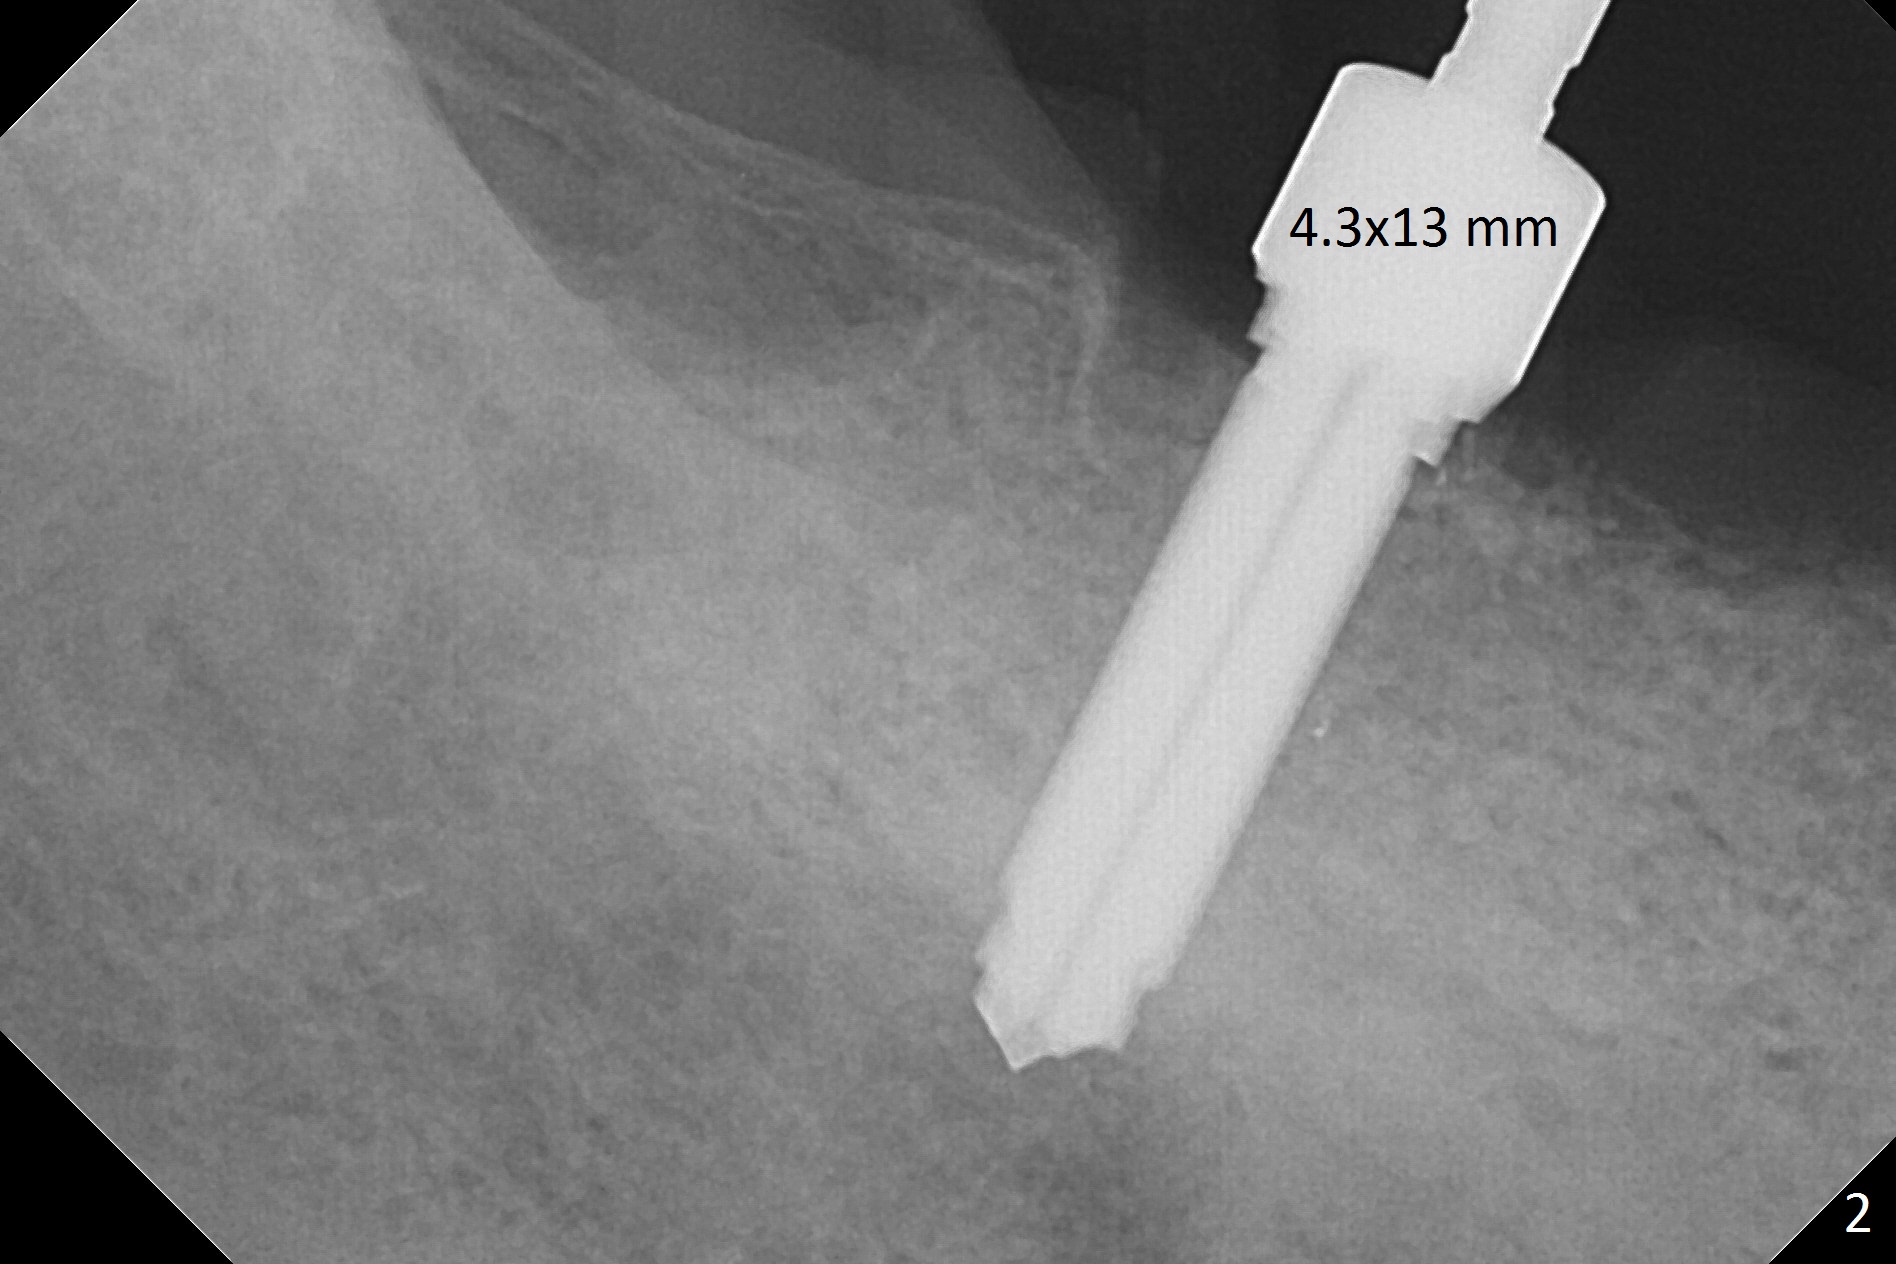

There are 2 challenges associated with #31 implant placement: indistinct Inferior Alveolar Canal (Fig.1-4) and difficulty in fabrication of a provisional (Fig.5). After placing a 5.5x13 mm implant (Fig.3 supracrestal (<)), it is removed for apical resection for ~ 2 mm; when it is reseated, it is subcrestal (Fig.5 <). A simplified temporary provisional (Fig.5 P) is fabricated around a 6.5x4(4) mm abutment (A) without adapting the lower RPD. The patient is advised not to wear the latter. When the socket heals, there will be 2 options: no provisional or a new one. The latter should have good retention to the abutment and no contact with the lower RPD in and out.